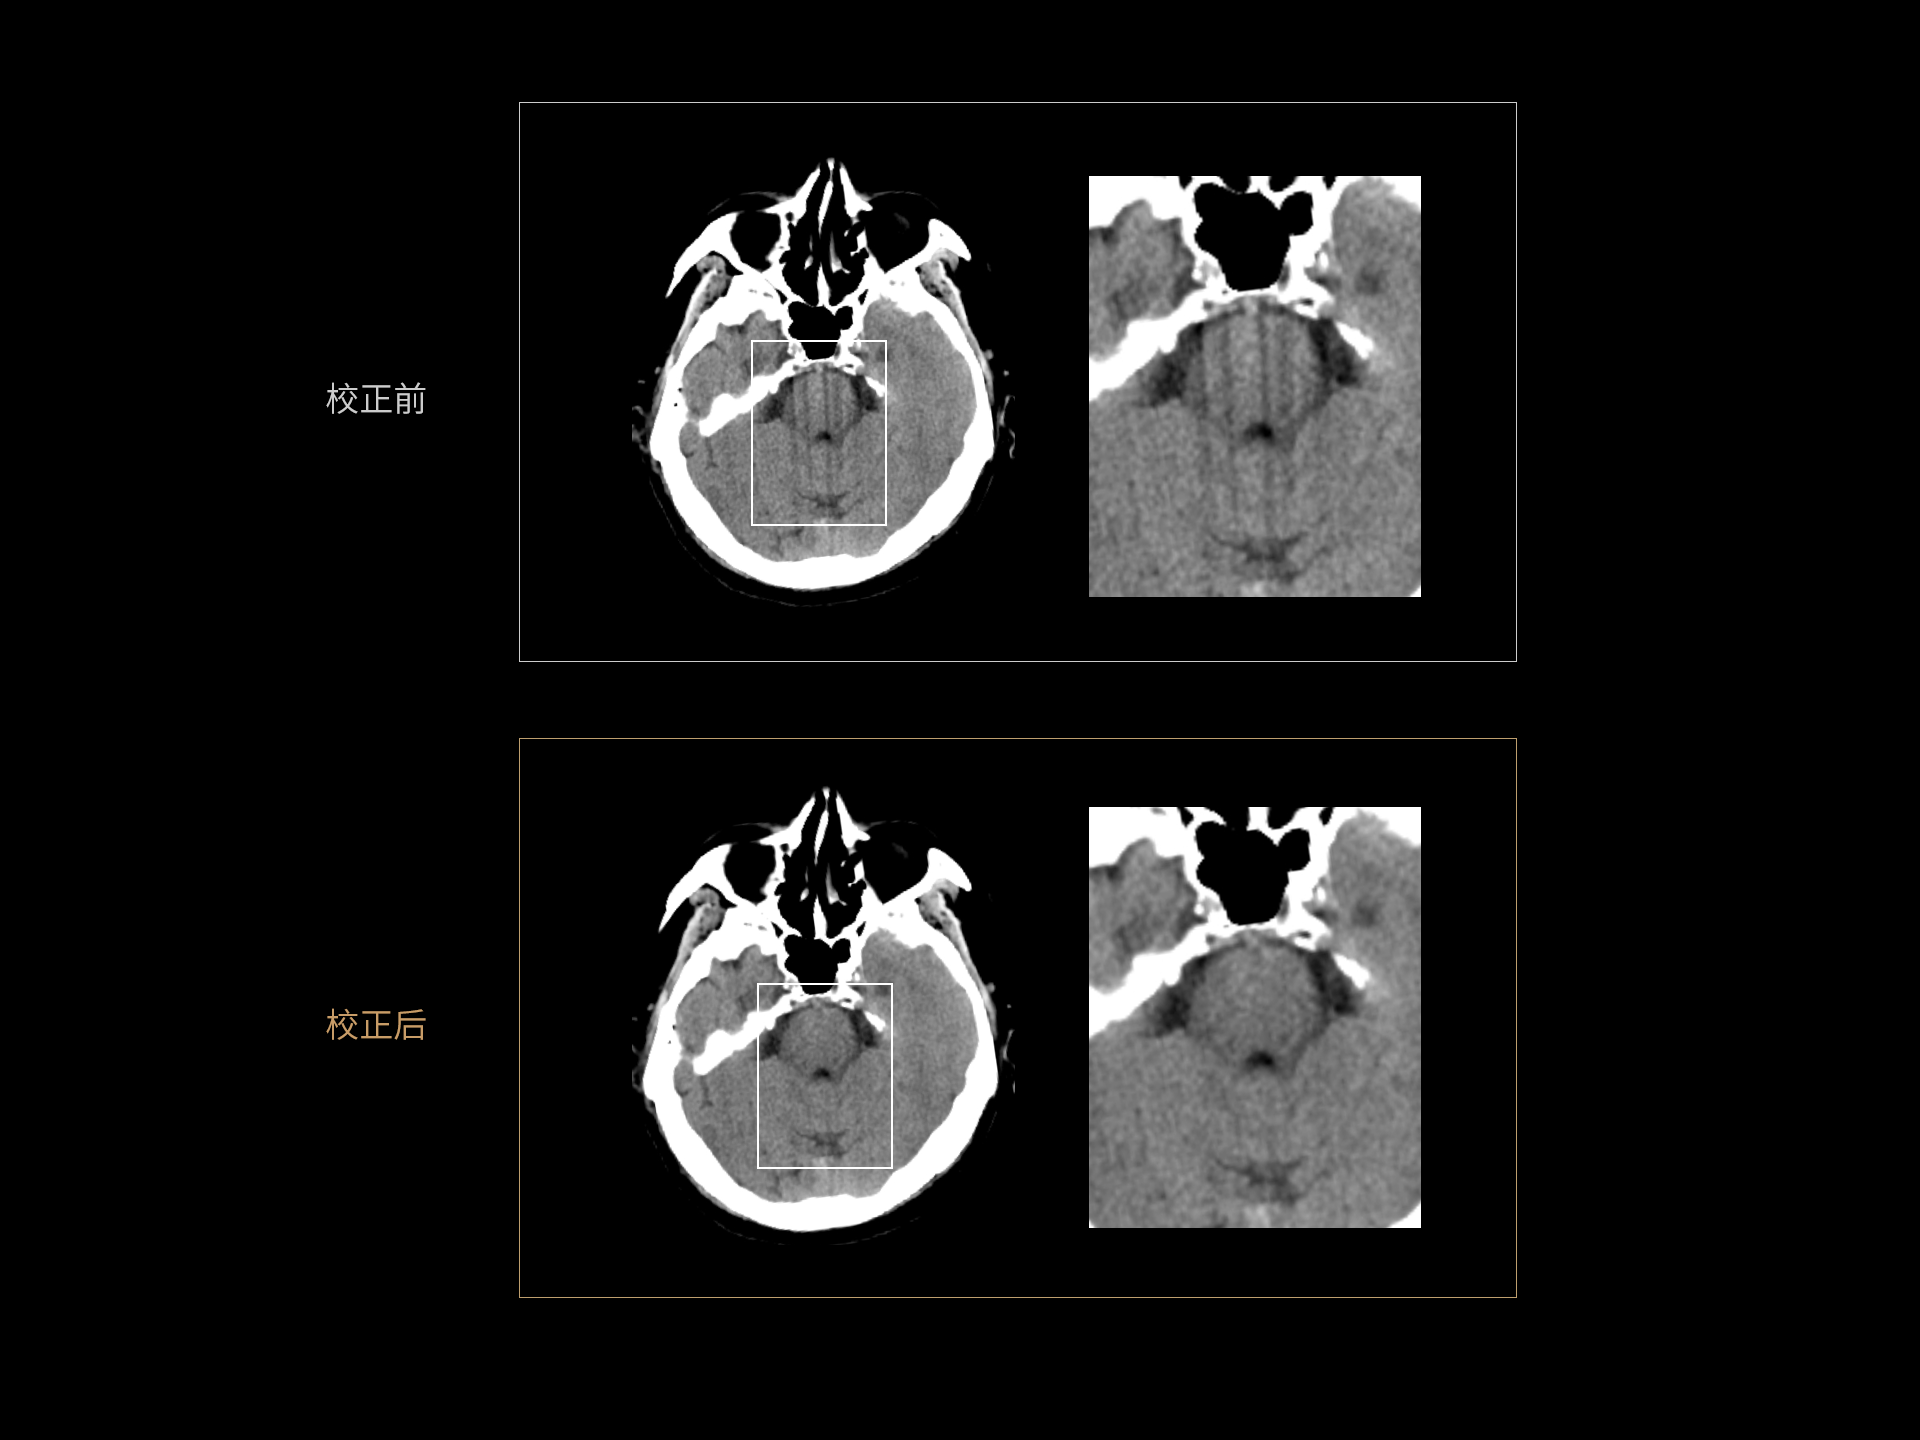

AI运动感知重建 消除头部运动伪影

Motion Freeze技术:基于深度学习技术校正头部运动伪影,保持头部结构清晰显示。

选用临床无运动伪影的图像作为金标准图像,模拟出不同场景下的运动形式,获得含有运动伪影的图像,从而解决了金标准数据与伪影数据的获取、匹配难题。Motion Freeze构建了独特的3D卷积神经网络,在去除运动伪影的同时,保障图像的空间与密度分辨率不受影响。

Motion Freeze临床应用范围广,可应用于头部平扫、增强、血管造影(CTA)和灌注(CTP)等临床场景;改善因疾病、紧张等因素导致的头部运动伪影,减少不必要的重复扫描、从而降低检查的辐射剂量。

Motion Freeze 技术优势

Motion Freeze 临床价值

AI 运动感知重建 Motion Freeze

头部运动深度学习重建:消除头部运动引起的条状伪影,还原脑部结构,利于准确诊断;去除运动伪影功能,可以减少重复扫描次数,提升工作效率。